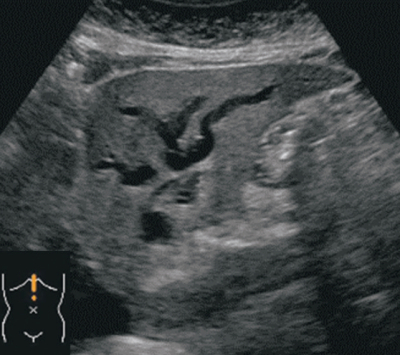

尿所見:蛋白(−)、糖(−)、潜血+、ビリルビン 2+。血液所見:赤血球 468万、Hb 13.9 g/dL、Ht 42%、白血球8,300、血小板21万。血液生化学所見:総ビリルビン 9.8 mg/dL、直接ビリルビン 6.2 mg/dL、AST 52 U/L、ALT 63 U/L、ALP 323 U/L(基準 38~113)、LD 242 U/L(基準 120~245)、γ-GT 282 U/L(基準 8~50)。免疫血清学所見:CRP 1.0 mg/dL、HBs抗原陰性、HCV抗体陰性。腹部超音波像を別に示す。